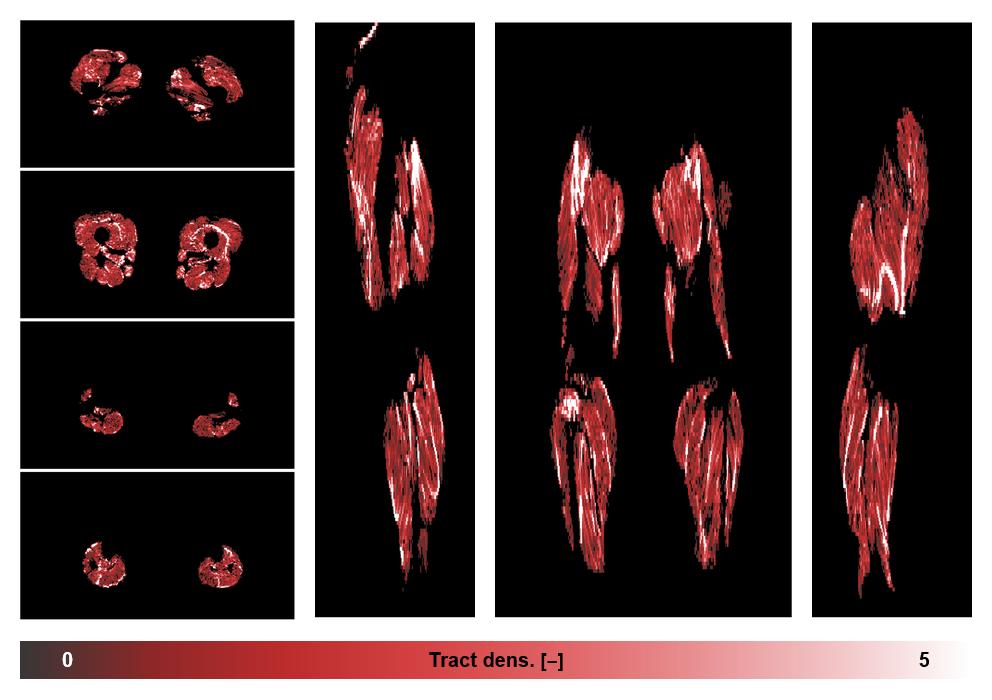

• Muscle fiber density map

Muscle fiber tract density map based on whole leg DTI based fiber tractography.